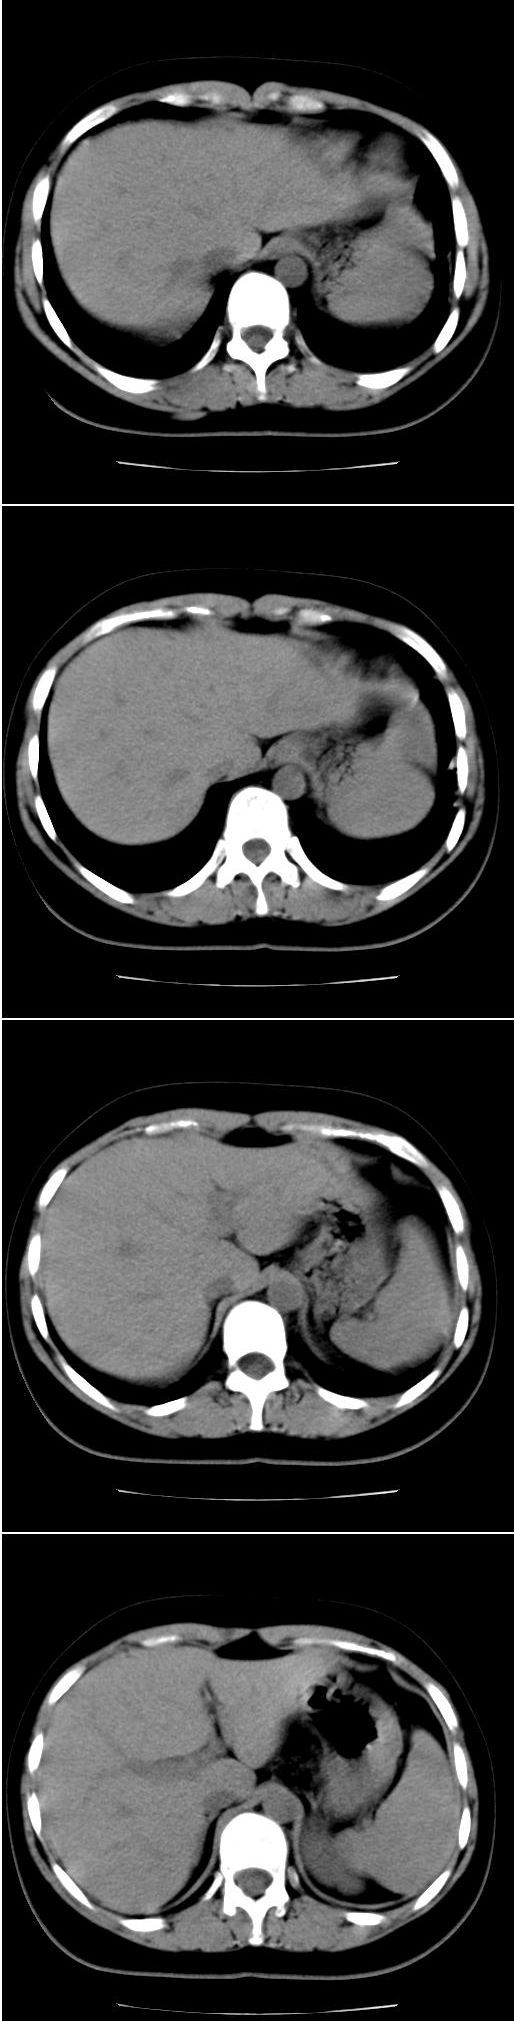

以下是引用光影相伴在2008-4-26 11:32:00的发言:[br]左肺继发性结核伴左肺上叶肺不张。建议:行纤维支气管镜检查排除支气管内膜结核。

以下是引用光影相伴在2008-4-26 11:32:00的发言:[br]左肺继发性结核伴左肺上叶肺不张。建议:行纤维支气管镜检查排除支气管内膜结核。

以下是引用zsl6918在2008-4-26 16:18:00的发言:[br]符合支气管内膜结核的诊断。

以下是引用光影相伴在2008-4-26 11:32:00的发言:[br]左肺继发性结核伴左肺上叶肺不张。建议:行纤维支气管镜检查排除支气管内膜结核。

以下是引用有风的日子在2008-4-26 13:54:00的发言:[br][quote]以下是引用光影相伴在2008-4-26 11:32:00的发言:[br]左肺继发性结核伴左肺上叶肺不张。建议:行纤维支气管镜检查排除支气管内膜结核。